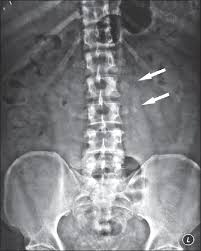

A transverse process fracture at the level of l5 is a surrogate marker of vertical instability of the pelvic fracture due to the attachment of the iliolumbar ligaments. Possible causes, signs and symptoms, standard treatment options and means of care and support. Transverse processes are used as lever arms by the deep spinal muscles to maintain posture and to induce rotation and lateral bending. It may occur as an avulsion fracture due to strong contracture of the muscles. Although the fracture is not associated with spinal cord damage and neurological deficits, the extreme force of the injury can cause visceral injuries and internal hemorrhage. The presence of other injuries might also be assessed due to the level of force needed to break the transverse process. In 78% of transverse process fractures, ct scanning showed that the fracture extended into the transverse foramen. Transverse process fractures caused by stress are likely under detected since even an acute transverse process fracture requires a high index of suspicion to be correctly identified(4,7). Here is an example of a patient with a benign looking transverse process fracture with an associated significant injury to the back. Transverse process fracture you have fractured a transverse process. Thoracic transverse process fractures (ttpfs) are injuries that go unnoticed during traditional autopsies, as demonstrated by a lack of medicolegal publications regarding ttpfs. We retrospectively reviewed the reports of lumbar spine and abdominopelvic ct scans from 2017 and 2018 to classify the types of spine fractures, their mechanism of injury, treatment and. Up to 60% of lumbar transverse process fractures identified on ct will be missed on plain radiographs.

Fractures Of The Thoracic And Lumbar Spine Orthoinfo Aaos from orthoinfo.aaos.org There is one on both sides of every vertebra in the… a transverse process fracture is quite a rare injury. A transverse process fracture is a break in 1 or more transverse process. Transverse process fracture is a rare and stable fracture of the spine. We retrospectively reviewed the reports of lumbar spine and abdominopelvic ct scans from 2017 and 2018 to classify the types of spine fractures, their mechanism of injury, treatment and. This may be done through diet and exercise. Transverse process fractures caused by stress are likely under detected since even an acute transverse process fracture requires a high index of suspicion to be correctly identified(4,7). Thoracic transverse process fractures (ttpfs) are injuries that go unnoticed during traditional autopsies, as demonstrated by a lack of medicolegal publications regarding ttpfs. Transverse processes are typically fractured in direct blows from athletics touch or impact from falls from bikes/motorbikes or by heights.

However, postmortem computed tomography (pmct) has made detection of this type of injury easy. There are two transverse processes that extend off each vertebra in the details: What is a transverse process fracture? It may occur as an avulsion fracture due to strong contracture of the muscles. It occurs as a result of sudden and extreme trauma. If ct confirms isolated injury lateral flexion/extension views are indicated to rule out dynamic instability. Vertebral angiography, performed in eight patients with fractures involving the transverse foramen, showed dissection or occlusion of the vertebral artery in seven (88%) instances. This part extends out from the side of the main body of the bone (called the vertebral body). A transverse process fracture at the level of l5 is a surrogate marker of vertical instability of the pelvic fracture due to the attachment of the iliolumbar ligaments. We retrospectively reviewed the reports of lumbar spine and abdominopelvic ct scans from 2017 and 2018 to classify the types of spine fractures, their mechanism of injury, treatment and. Up to 60% of lumbar transverse process fractures identified on ct will be missed on plain radiographs. In 78% of transverse process fractures, ct scanning showed that the fracture extended into the transverse foramen. Transverse process fractures identified on helical computed tomography (ct) scans without the presence of any other fracture or.